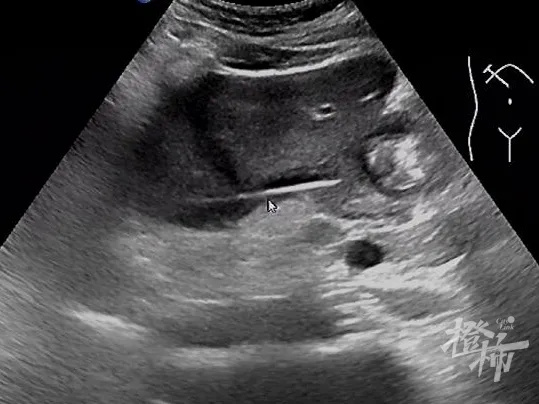

陈公英主任团队给高先生做了相应检查,最后,通过CT和B超检查发现他的肝脏竟然有一个8cmx6cm的脓肿,随后安排至超声医学科做了肝脓肿穿刺引流术。术后,高先生不适感慢慢缓解,2周后复查B超,医生竟在高先生的肝脏脓肿处发现了一根牙签

高先生反复回忆,才想起一桩旧事。原来高先生有饮酒习惯,吃完饭后习惯用牙签清理牙齿。最近有一次吃完饭严重醉酒,醒来后感觉肚子不舒服,后面好转后也没当回事。很有可能就是那次误吞了牙签,牙签进入胃后又穿透了胃壁,插进肝脏从而形成了肝脓肿。当脓肿消退后,被脓液包裹着的异物(牙签)自然就显现出来了。